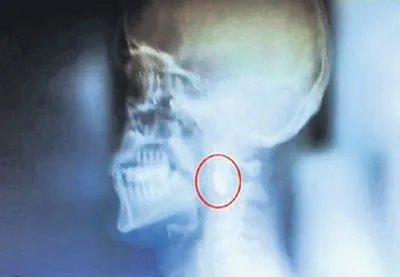

İsmail Acur (39) 15 Temmuz 2016'daki darbe girişiminde İstanbul Saraçhane'de hainlere karşı en ön safta direnişe katıldı. İBB binası önünde darbeci askerlerin G3 silahından çıkan mermiyle başından vurulan Acur sağ gözünü kaybetti. Şahdamarının yanına saplanan mermi tehlikeli olduğu için vücudundan alınamadı. 7 yıldır o mermiyle yaşayan Acur, darbe girişimin yıldönümü yaklaşırken SABAH'a konuştu:

X-Ray'den geçtiğimde alarm çaldı, polis yanıma geldi. Gazi olduğumu söyledim, silahım olup olmadığını sordu. 'Bir tane kurşunum var' deyince onu istediler. 'Ben yıllarca uğraştım, çıkaramadım, siz çıkarabilir misiniz' deyince gülüştük. Sağlığımı kaybetsem de gururluyum. Boynumda, şahdamarımın hemen yanı başında bir şeref madalyası var. Bu benim için öyle kutsal ki, değerini kelimelerle ifade edemem. Boynumdaki kurşunun hareket ettiğini hissederim. Bir milim daha oynasaydı belki de şehit olma onuruna erişecektim. Bir ömür boyu, mezara kadar yanımda olacak, onur duyacağım bir şeref madalyam var. Milletimizin, vatanımızın hürriyet belgesi bu.